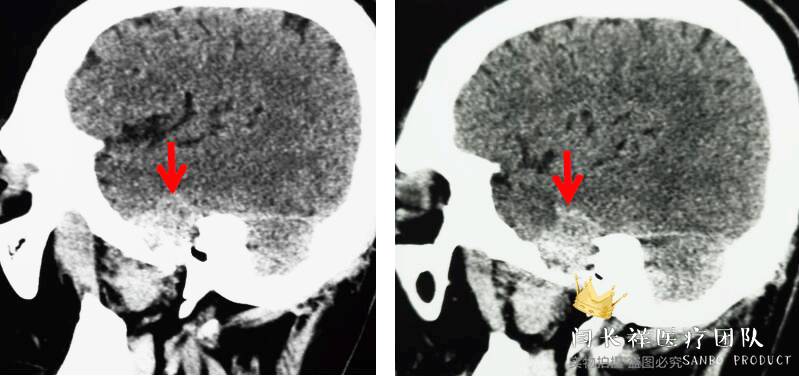

术前矢状位CT。

中颅窝-颞下窝占位

术前冠位CT骨窗像示右侧中颅窝底骨质被肿瘤侵蚀破坏。